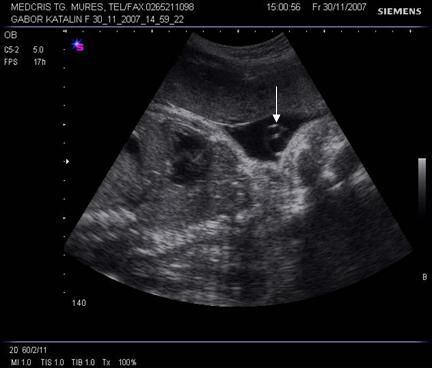

Fig. nr. 149 Planul I de sectiune transversala.

Planul

II demonstreaza ventriculii laterali hipoecogeni si parte din plexurile

choroide ecogene.

Fig. nr. 150. Planul II de sectiune transversala a craniului fetal.